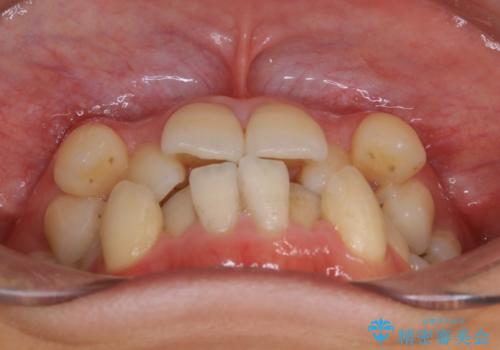

- 以前からコンプレックスだった八重歯の治療を主訴にご来院されました。

検査の結果、抜歯をすることでスペースを作って並べる方法が選択され、ワイヤー装置を用いた治療を開始することとなりました。

叢生の度合いが重く、抜歯が必要なケース。八重歯の部分以外には大きな問題は認められなかったため、劇的変化が起こる治療でも比較的短期間で終了することができました。